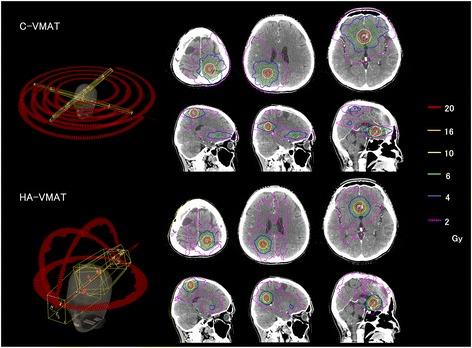

The HyperArc VMAT (HA-VMAT) planning approach was newly developed to fulfill the demands of dose delivery for brain metastases stereotactic radiosurgery. We compared the dosimetric parameters of the HA-VMAT plan with those of the conventional VMAT (C-VMAT).

For 23 patients (1-4 brain metastases), C-VMAT and HA-VMAT plans with a prescription dose of 20-24 Gy were retrospectively generated, and dosimetric parameters for PTV (homogeneity index, HI; conformity index, CI; gradient index, GI) and brain tissue (V-V) were evaluated. Subsequently, the physical characteristics (modulation complexity score for VMAT, MCSV; Monitor unit, MU) of both treatment approaches were compared.

HA-VMAT provided higher HI (1.41 ± 0.07 vs. 1.24 ± 0.07, p < 0.01), CI (0.93 ± 0.02 vs. 0.90 ± 0.05, p = 0.01) and lower GI (3.06 ± 0.42 vs. 3.91 ± 0.55, p < 0.01) values. Moderate-to-low dose spreads (V-V) were significantly reduced (p < 0.01) in the HA-VMAT plan over that of C-VMAT. HA-VMAT plans resulted in more complex MLC patterns (lower MCSV, p < 0.01) and higher MU (p < 0.01).

HA-VMAT plans provided significantly higher conformity and rapid dose falloff with respect to the C-VMAT plans.

新开发的 HyperArcVMAT(HA-VMAT)计划方法旨在满足脑转移立体定向放射外科的剂量传递要求。我们比较了 HA-VMAT 计划和传统 VMAT(C-VMAT)的剂量学参数。

回顾性地为 23 名患者(1-4 个脑转移灶)生成了 C-VMAT 和 HA-VMAT 计划,处方剂量为 20-24Gy,并评估了 PTV(均匀性指数、HI;适形指数、CI;梯度指数、GI)和脑组织(V-V)的剂量学参数。随后,比较了两种治疗方法的物理特性(VMAT 的调制复杂度评分、MCSV;监测单位、MU)。

HA-VMAT 提供了更高的 HI(1.41±0.07 对 1.24±0.07,p<0.01)、CI(0.93±0.02 对 0.90±0.05,p=0.01)和更低的 GI(3.06±0.42 对 3.91±0.55,p<0.01)值。HA-VMAT 计划中的中低剂量分布(V-V)明显减少(p<0.01)。HA-VMAT 计划导致更复杂的 MLC 模式(较低的 MCSV,p<0.01)和更高的 MU(p<0.01)。

HA-VMAT 计划在 C-VMAT 计划的基础上提供了更高的一致性和更快的剂量衰减。